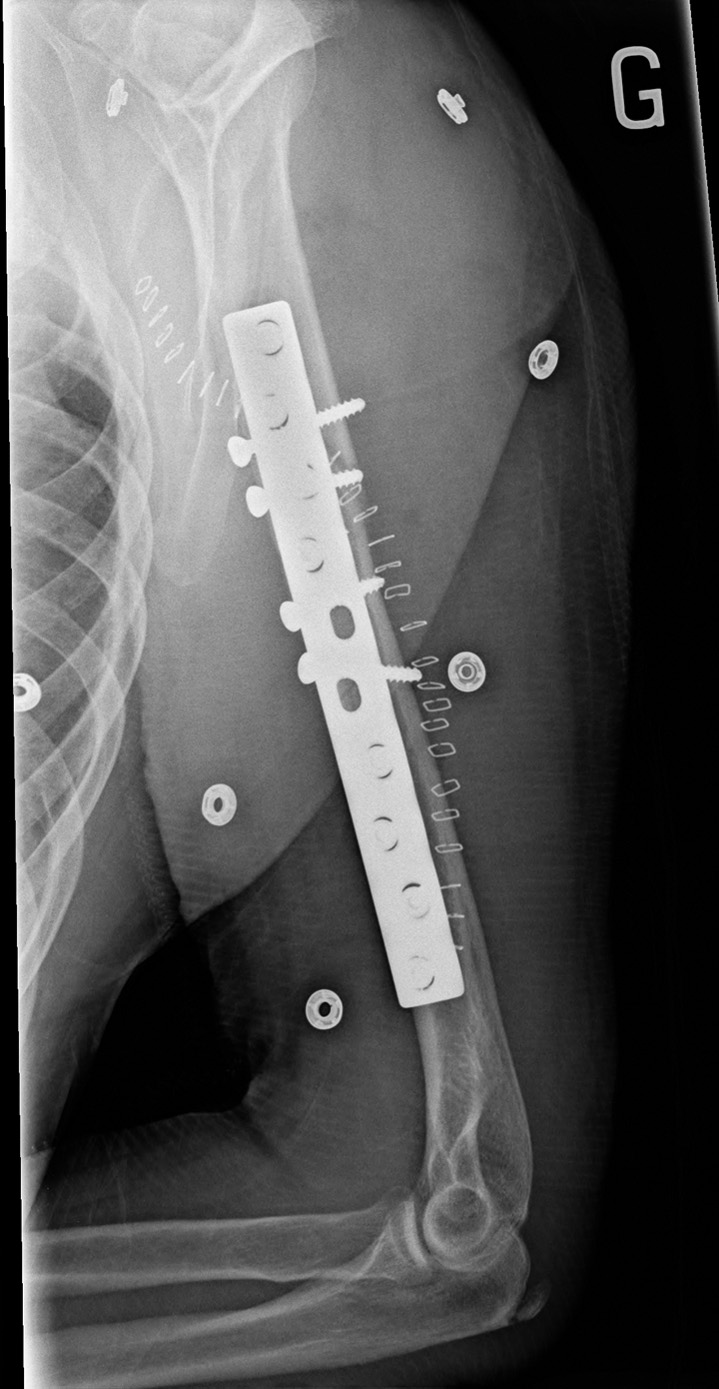

59-year-old male:

Postoperative control of a torsion trauma of the upper limb.

Humeral shaft fracture

Postoperative radiograph following the open reduction and internal fixation of a comminuted fracture of the humeral shaft. The fracture is reduced to an anatomic position and 4 interfragmentary screws are installed to secure the reduction.

In addition to the 4 interfragmentary screws, a plate and its screws are then added to strenghten the fixation.